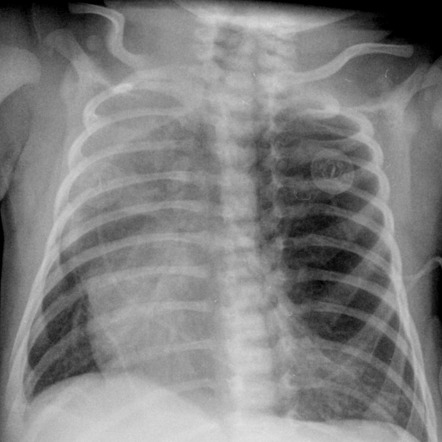

Congenital lobar emphysema | Radiology Case | Radiopaedia.org

ENFISEMA LOBAR CONGENITO PDF  Congenital lobar emphysema | Radiology Case | Radiopaedia.org

Lobar holoprosencephaly | Radiology Case | Radiopaedia.org  Congenital lobar emphysema | Eurorad

Congenital lobar emphysema | Eurorad  Lobar collapse demystified: the chest radiograph with CT correlation | Postgraduate Medical Journal

Congenital lobar emphysema | Image | Radiopaedia.org  Shopping for tisart - YouTube

Lobar hemorrhage | Radiology Reference Article | Radiopaedia.org  Congenital Lobar Emphysema - The Clinical Advisor

Congenital Lobar Emphysema - The Clinical Advisor  Lobar Holoprosencephaly in 2020 | Retroverted uterus, Cleft lip and palate, Cleft lip

Congenital lobar emphysema | Image | Radiopaedia.org  Lobar haemorrhage | Image | Radiopaedia.org

Congenital lobar overinflation | Radiology Reference Article | Radiopaedia.org  CONGENITAL LOBAR EMPHYSEMA | buyxraysonline

CONGENITAL LOBAR EMPHYSEMA | buyxraysonline  ENFISEMA LOBAR CONGENITO PDF

39 Congenital Lobar Emphysema | Radiology Key  Right upper lobe consolidation: an unusual complication of an uneventful endotracheal intubation

Congenital lobar emphysema | Eurorad  Home - Lobar Incorporated

Congenital Lobar Emphysema Article  PPT - Chest X-Ray Interpretation for the Internist PowerPoint Presentation - ID:934924

Congenital Lobar Emphysema - Metabolic Disorders - My Fertility Guide  Congenital Lobar Emphysema | Thoracic Key

Congenital Lobar Emphysema | Thoracic Key  a CT showing large lobar hemorrhage at the left parietal lobe. b A | Download Scientific Diagram

Congenital lobar emphysema: diagnostic and therapeutic challenges | BMJ Case Reports  Lobar hemorrhage | MedLink Neurology